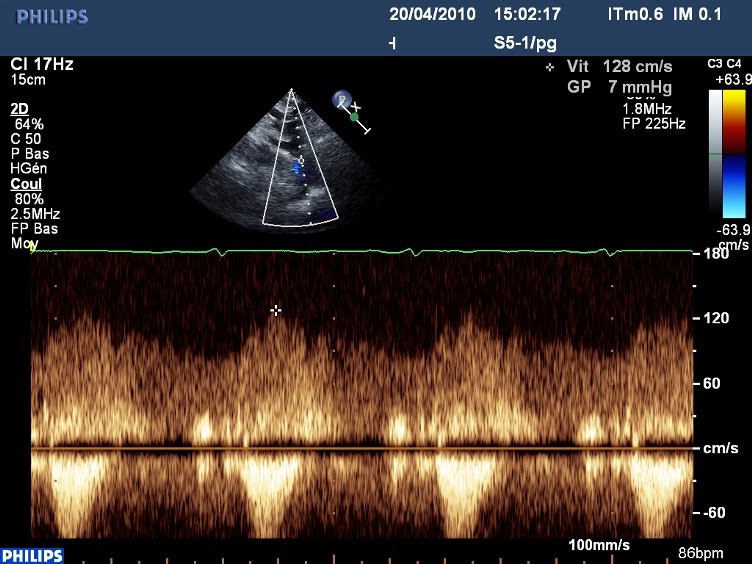

Voilà ce que ça donne en Doppler continu: